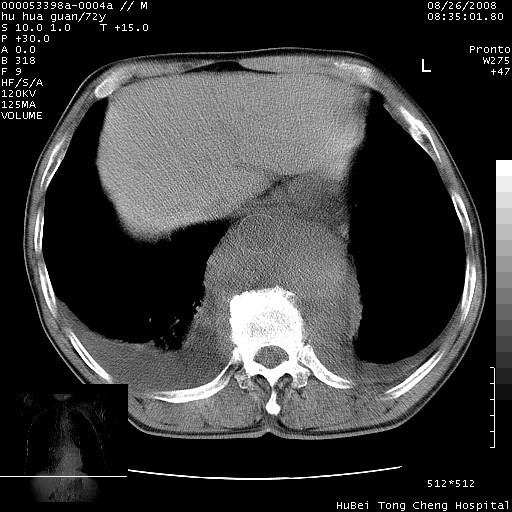

降主动脉前移位,后纵隔占位

后纵隔占位,降主动脉前移位;双侧胸腔积液;应排外食管病变侵犯血管可能;

可以明确的说。肯定不是主动脉夹层破裂出血!考虑为淋巴瘤或间叶组织来源的恶性肿瘤可能性大。右肺小结节建议薄层观察,如能发现恶性征象,那椎前改变就考虑为转移所致。至于双侧少量胸水乃静脉血回流受阻所致。

1、右上肺结节病变,肺泡癌不除外,请随诊;左下肺近后纵隔病变,考虑纵隔型肺癌侵犯大血管可能;

2、右下肺背段少许炎症,双侧胸腔积液,右下肺纤维索条。

建议排除结核引起的冷脓肿。